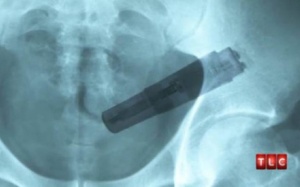

Nếu không tiến hành phẫu thuật gắp bỏ dị vật mắc kẹt kịp thời thì người đàn ông này có thể sẽ bị ảnh hưởng tới cơ quan nội tạng bên trong cơ thể.